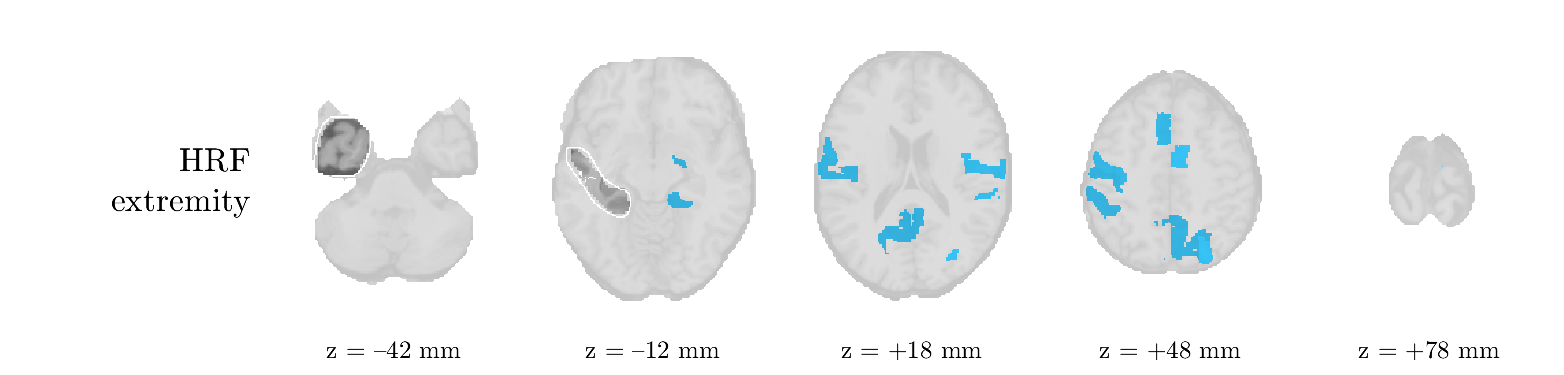

Patient 2

We analyze the solution with sources, and show the results in Figure 3 and 4. As for patient 1, we found a source which is strongly correlated to the MWF envelope, and which had a mostly low-frequency behavior characteristic for spikes. The topography is mostly uninformative, and does not clearly correspond to the patient’s clinical data. The third source is mostly present at both sides of the head, is very sparsely active in time, and has a high-frequency content: this is most likely an artifact due to the neck muscles. Again, there is one of the highest-entropy HRFs which belongs to a ROI in the IOZ. Now, the waveform is clearly resolved from the other HRFs, through the strong initial dip (before 0 seconds). Such a dip is sometimes observed in HRFs, but its underlying physiological mechanism is not yet fully understood. It is possible that this dip reflects altered vascular autoregulation near the IOZ (cfr. the explanation in the Section 1 of the main text), or a rapid depletion in oxygen due to IED generation (before the IED becomes visible on the EEG). Figure 4 furthermore shows that the IED-related component is significantly active in parts of the IOZ, and deactive in others. As mentioned earlier, this deactivation may or may not be due to errors in sign correction. Interestingly, the ROI with the high alteration in neurovascular coupling is distinct from both the activated and deactivated ROIs.